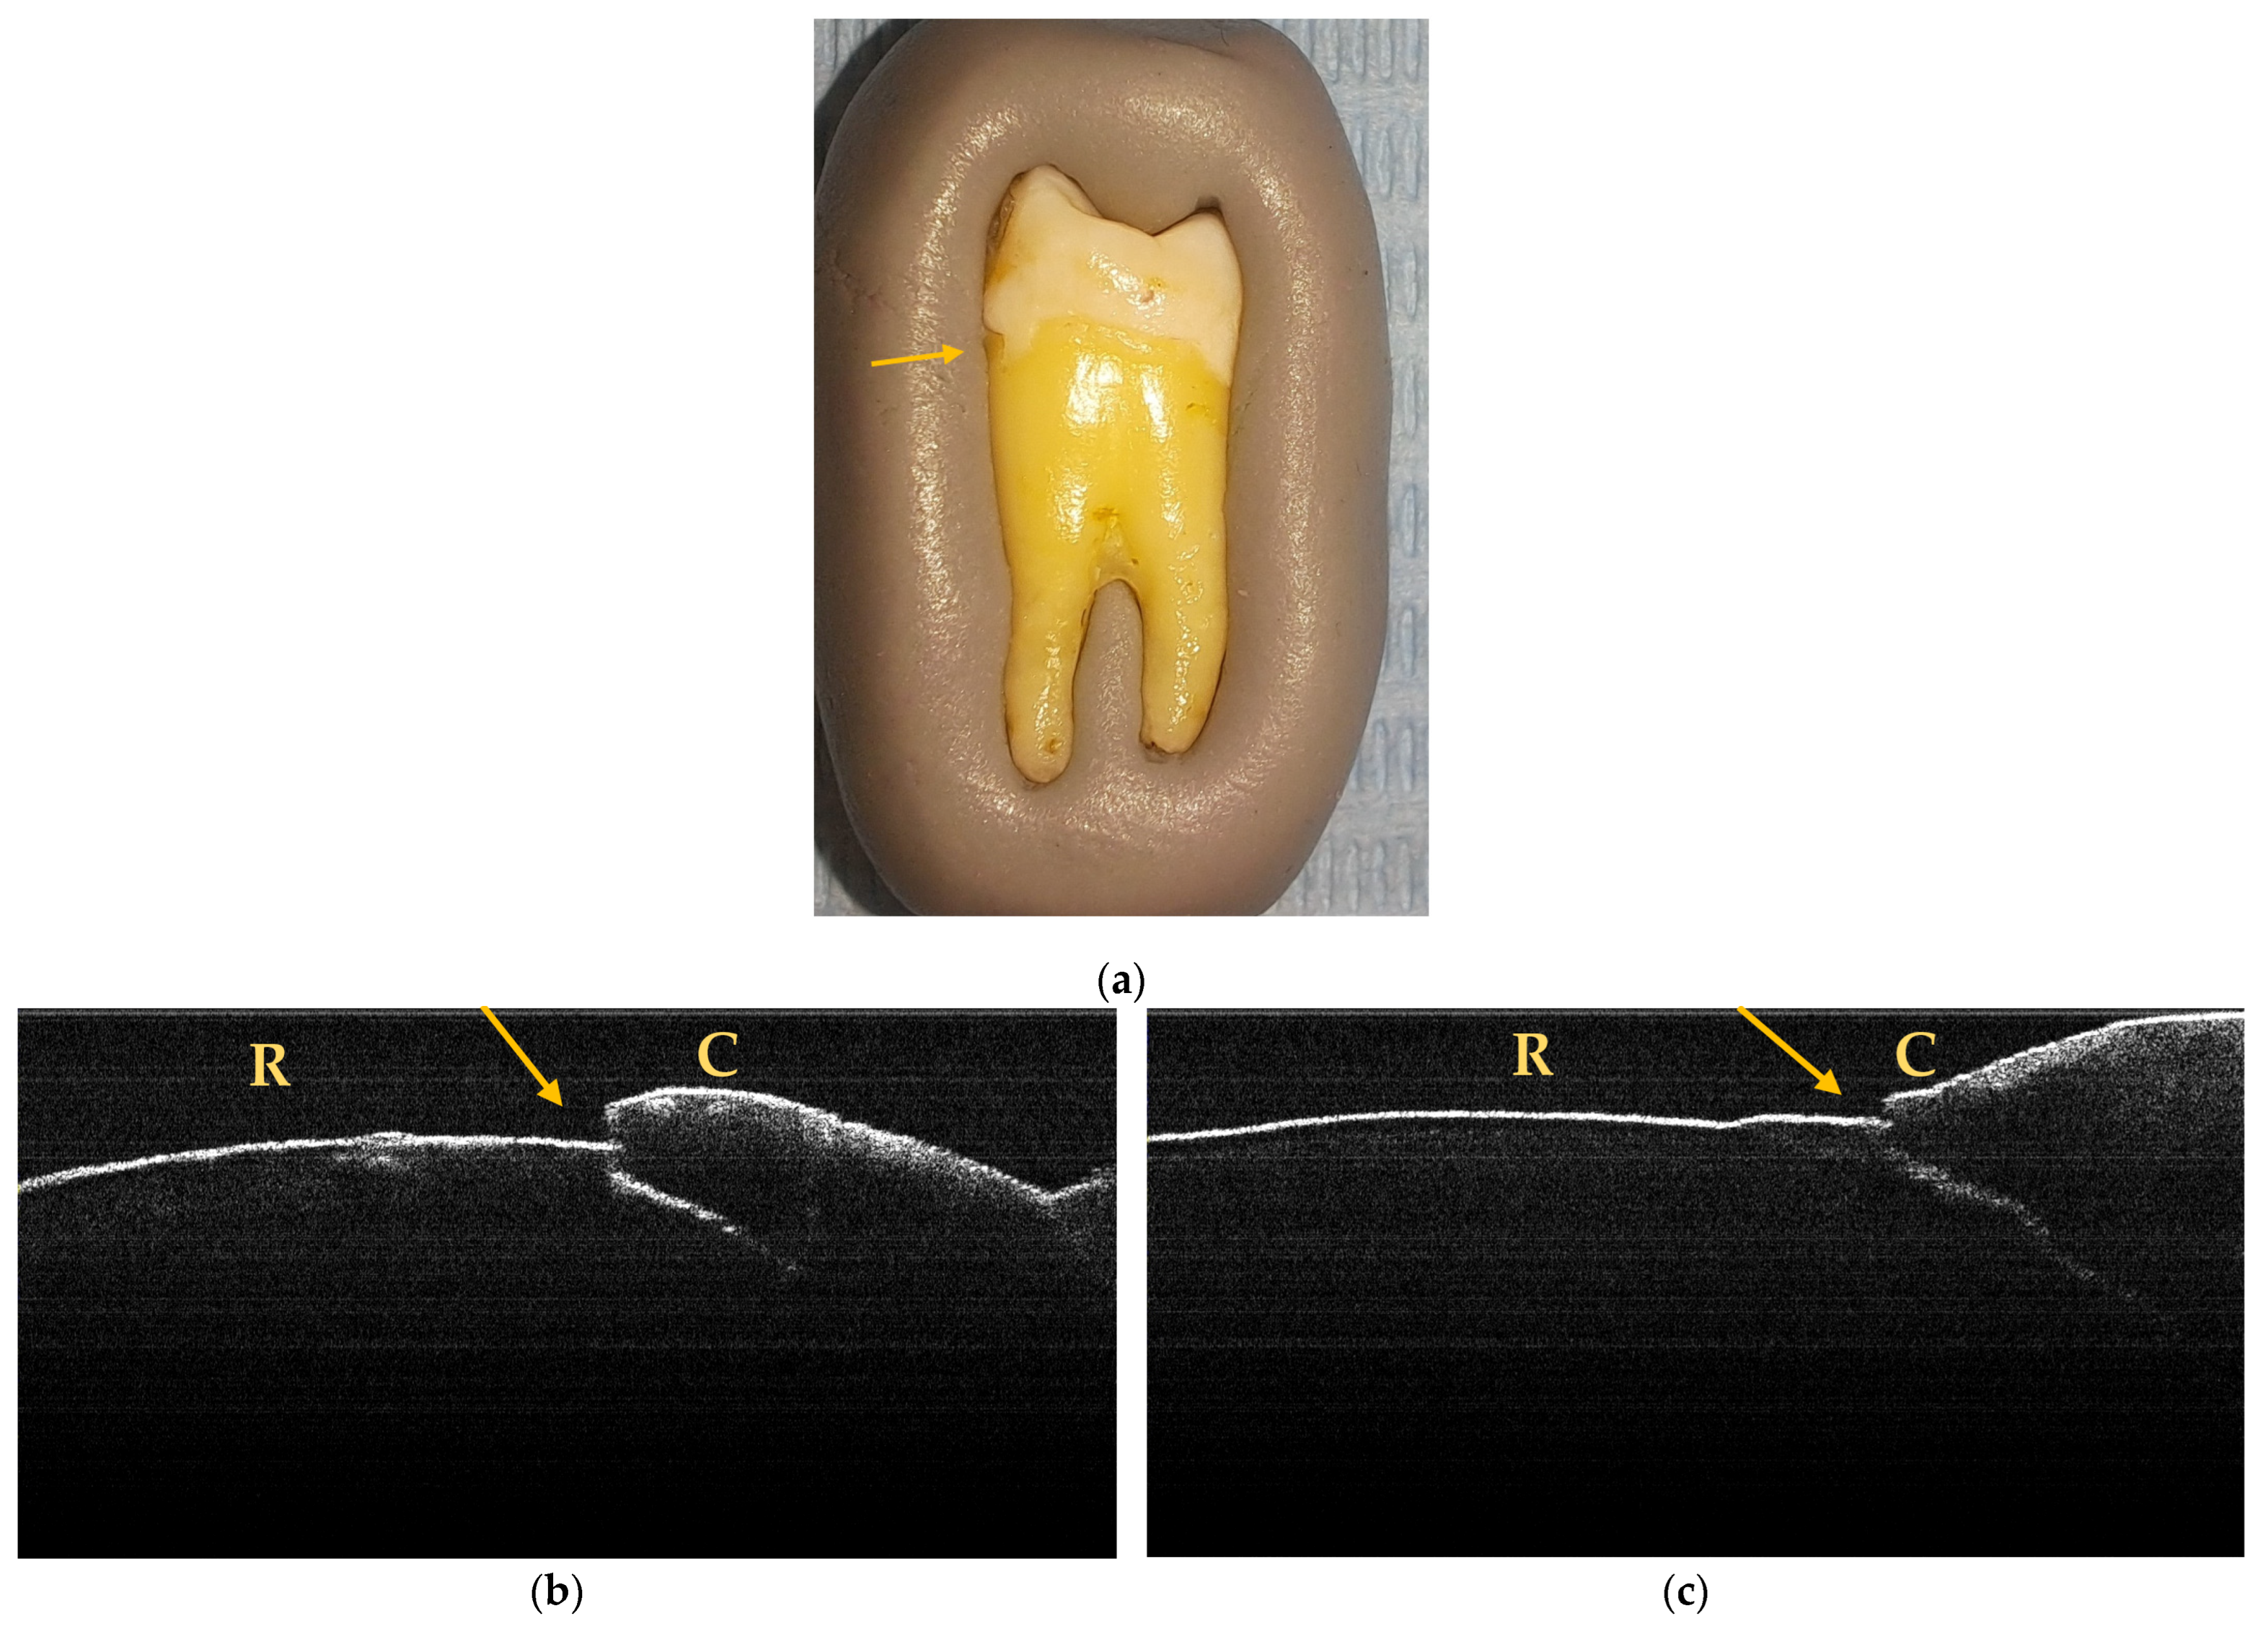

A maximum of 512 OCT images was taken for each dental surface examined. Figure 3, Figure 4 and Figure 5 present specific OCT images of teeth with macroscopically identified NCCLs, but also specific OCT images of teeth in which the NCCLs were not visible macroscopically. In each figure depicting the OCT images obtained, the position of the dental crown is marked with the letter C, the position of the root is marked with the letter R, and the arrow indicates the NCCL.

Figure 5.

OCT images of an irregular NCCL, indicated by the arrows.

Through macroscopic and OCT examination, 34 NCCLs were identified, of which 14 were in incisors (41.18%) and 20 in premolars (58.82%). It was observed that, in the end, 6 teeth (1 incisor and 5 premolars) presented several NCCLs that were visible macroscopically and on OCT examination (Figure 6).

Figure 6.

Macroscopic and OCT aspects of PM6: (a) macroscopic image showing superficial NCCL on the buccal surface, indicated by the arrow; (b) OCT image of the buccal surface where an NCCL is observed, indicated by the arrow; (c) OCT image of the mesial surface where an NCCL is observed, indicated by the arrow.